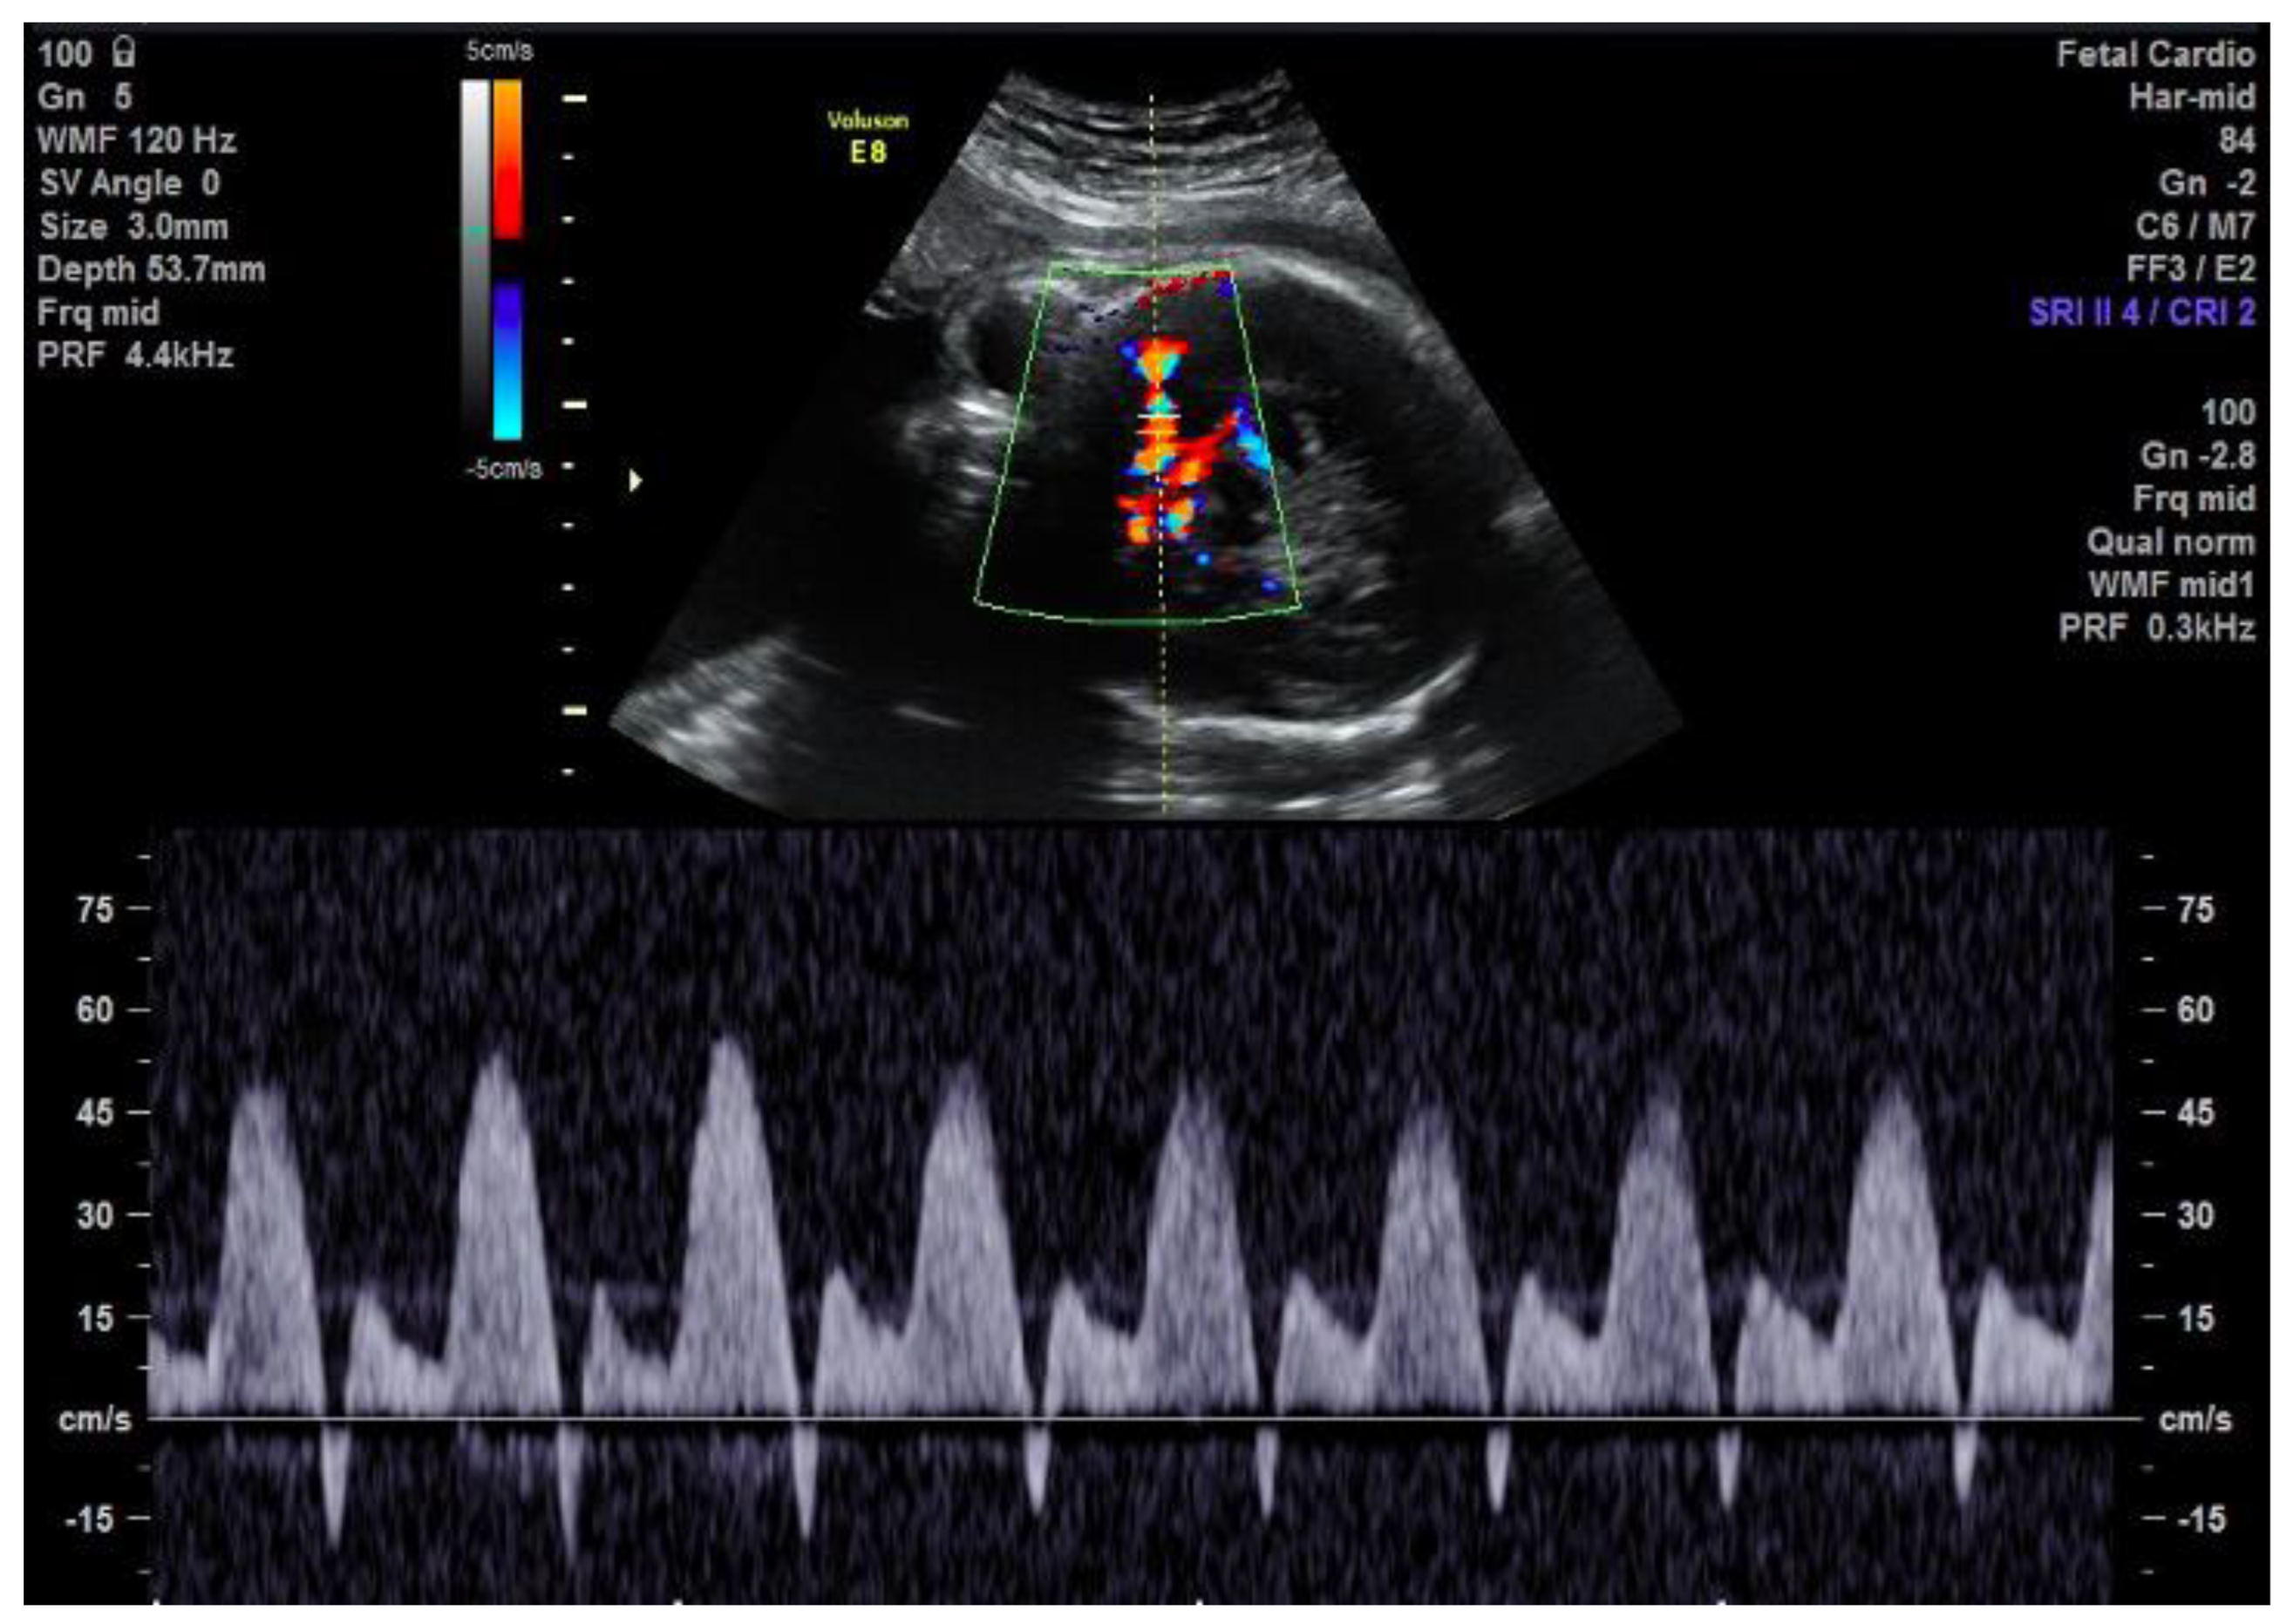

2. Case Description